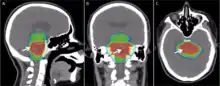

Delivery parameters of a prescribed dose are determined during treatment planning (part of dosimetry). Treatment planning is generally performed on dedicated computers using specialized treatment planning software. Depending on the radiation delivery method, several angles or sources may be used to sum to the total necessary dose. The planner will try to design a plan that delivers a uniform prescription dose to the tumor and minimizes dose to surrounding healthy tissues.

An enhancement of virtual simulation is 3-dimensional conformal radiation therapy (3DCRT), in which the profile of each radiation beam is shaped to fit the profile of the target from a beam's eye view (BEV) using a multileaf collimator (MLC) and a variable number of beams. When the treatment volume conforms to the shape of the tumor, the relative toxicity of radiation to the surrounding normal tissues is reduced, allowing a higher dose of radiation to be delivered to the tumor than conventional techniques would allow.[5]

Intensity-modulated radiation therapy (IMRT) is an advanced type of high-precision radiation that is the next generation of 3DCRT.[60] IMRT also improves the ability to conform the treatment volume to concave tumor shapes,[5] for example when the tumor is wrapped around a vulnerable structure such as the spinal cord or a major organ or blood vessel.[61] Computer-controlled x-ray accelerators distribute precise radiation doses to malignant tumors or specific areas within the tumor. The pattern of radiation delivery is determined using highly tailored computing applications to perform optimization and treatment simulation (Treatment Planning). The radiation dose is consistent with the 3-D shape of the tumor by controlling, or modulating, the radiation beam's intensity. The radiation dose intensity is elevated near the gross tumor volume while radiation among the neighboring normal tissues is decreased or avoided completely. This results in better tumor targeting, lessened side effects, and improved treatment outcomes than even 3DCRT.